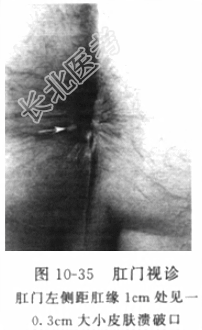

- [材料题] 患者男性,46岁,因“反复肛周左侧流脓血1个月余”入院。患者于1个多月前始间断出现肛门左侧流脓血水,有时伴肛周疼痛,当时未予重视,自行口服“头孢菌素”等“消炎”,症状有所好转,但不久又再度出现上述症状。本次就诊我院门诊,拟“肛瘘”收住入院。病程中无发热、寒战、便血、腹痛、腹泻、血尿等不适。发病以来,一般情况佳,大小便无异常。追溯病史,患者述1年前因“肛周脓肿”行手术切开治疗。体格检查体温(T)36.5℃,呼吸(R)18次/分,脉搏(P)72次/分,血压(BP)125/80mmHg。神志清楚,皮肤干燥,巩膜无黄染。腹部平坦,无压痛、反跳痛,肠鸣音无增强或减弱。膝胸位直肠检查:视诊(图10-35)见双侧臀部外形对称,肛门居中,膝胸位7点距肛缘1cm处见一0.3cm大小皮肤溃破口,指诊于7点处扪及条索样物直至对应肛窦处,直肠腔内未触及占位性病变,退出时指套无染血。辅助检查:血常规示白细胞8.9×10⁹/L,中性粒细胞80%,其他实验室检验结果包括肝肾功能、电解质和肿瘤标志物结果未见异常。全结肠镜检查未见结肠内病变,直肠超声内镜检查(图10-36)见直肠肛管后方瘘管。